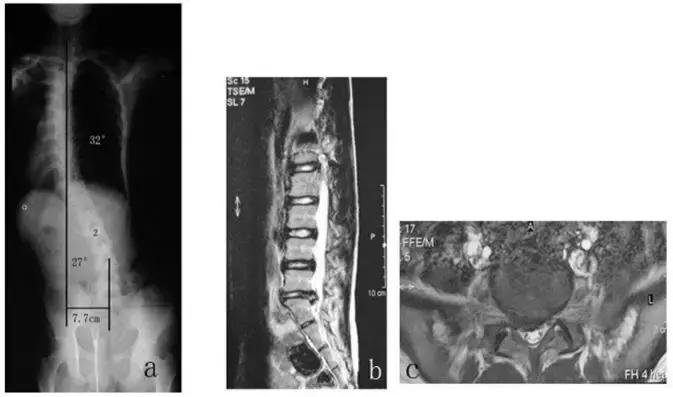

可以看下面这张图(图文引用于文献【1】),患者为右侧L5-S1间盘突出,术前脊柱侧弯非常严重!上半身重心偏移也非常严重!

下方左图是术后即刻的,可以看到侧弯已经大部分恢复了!下方右图是术后2.5年的,侧弯基本上完全恢复!